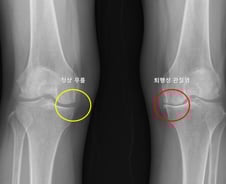

한쪽 무릎에 퇴행성 관절염이 생긴 환자는 다른쪽 무릎에도 똑같은 병이 생기지 않을지 불안에 떨어야 했다. 많은 환자가 한쪽 무릎에 관절염이 생긴 뒤 수년 내 반대쪽 무릎에서도 통증, 구조적 변화가 나타나는 경험을 한다. 하지만 이러한 양측성 진행이 모든 환자에게서 똑같이 나타나지 않아, 이를 예측하려는 연구는 부족했다. 그런데 서울대병원 연구팀이 이런 예측을 가능하게 하는 머신러닝 기반 모델을 개발하는 데 성공했다. 서울대병원 정형외과 노두현 교수팀(김지산 연구원)은 한쪽 무릎에 퇴행성 관절염이 있는 환자들을 대상으로 반대쪽 무릎에서 퇴행성 관절염이 발생할 가능성을 예측하는 머신러닝 모델을 개발했다고 9일 발표했다. 연구는 미국의 대규모 관절염 추적 코호트인 OAI(Osteoarthritis Initiative)와 MOST(Multicenter Osteoarthritis Study) 데이터셋를 기반으로 진행됐으며, 4~5년간 추적 관찰된 편측 무릎 퇴행성 관절염 환자 1353명을